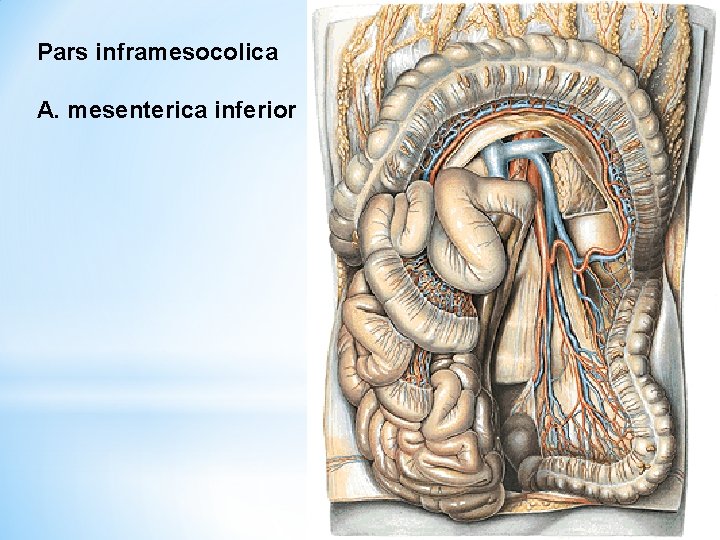

Pars inframesocolica A. mesenterica inferior